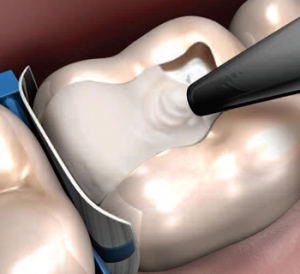

Знает ли врач технологию лечения кариеса по современным стандартам, умеет ли правильно ее применять - об этом пациент может только догадываться. Сидя в стоматологическом кресле с открытым ртом. Вы полностью доверяетесь врачу и надеетесь на благополучный исход лечения. Надейтесь, но не оставайтесь безучастным к тому, что делают с вашими зубами, особенно если вы впервые на лечении у вашего врача. Обратите особое внимание, - как врач препарирует (сверлит) ваш зуб. Здесь главное, чтобы зуб не перегрелся. Для этого необходимо охлаждение бора (сверла) и тканей зуба во время препарирования водой, а само препарирование должно быть прерывистым, без сильного давления. Врач во время препарирования должен использовать различные по назначению стоматологические инструменты: высокоскоростные наконечники (они при работе издают тихий свист), так называемые "турбины" - в них бор вращается со скоростью до 250 000 оборотов в минуту - предназначены для препарирования очень твердой эмали и плотного дентина с обязательным охлаждением. Низкоскоростные наконечники (они при работе издают звук похожий на урчание и жужжание одновременно) - предназначены для удаления размягченного кариесом дентина.